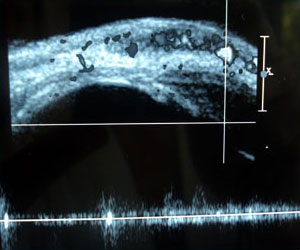

Ante duda diagnóstica o para objetivar el tamaño de la lesión el examen de primera elección por su acceso,

bajo costo y facilidad de realizar es la ecografía con doppler. Este examen puede ver las características

tumorales de la lesión, los shunts arteriovenosos propios del período de proliferación, calcular el volumen

de la lesión y determinar estructuras comprometidas.